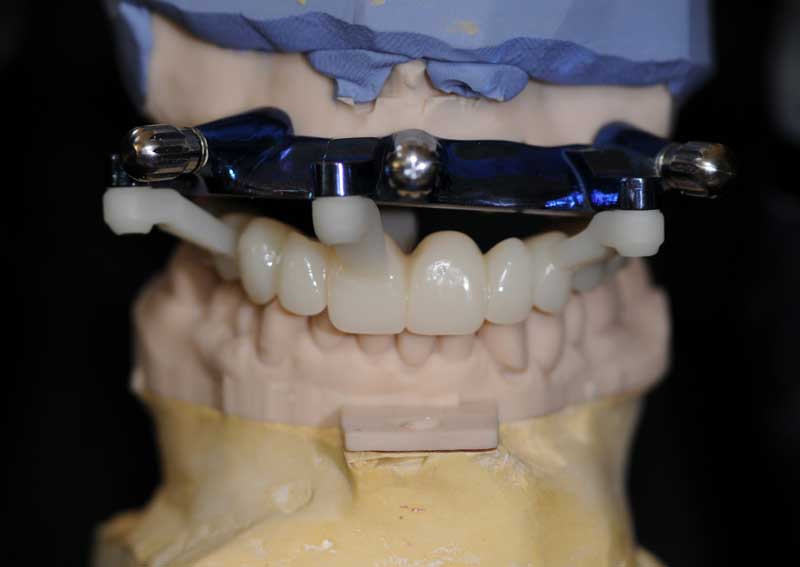

Prova estetica montaggio

Posizionamento tramite fissazione alla guida primaria del provvisorio, realizzato con resina stampata della Graphy

Controllo a 2 giorni, si noti ancora il gonfiore del viso